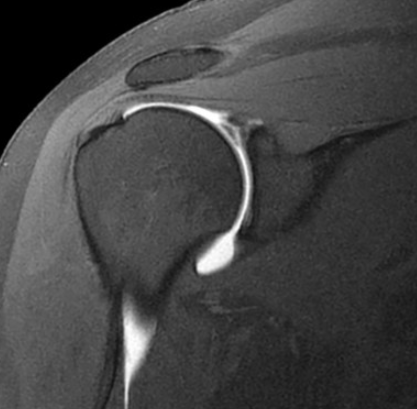

Acromio-humeral interval

• >12 mm: shoulder dislocation, inferior subluxation

• 8-12 mm : normal

• 6-7 mm: thinning of supraspinatus tendon

• <6 mm: supraspinatus tear